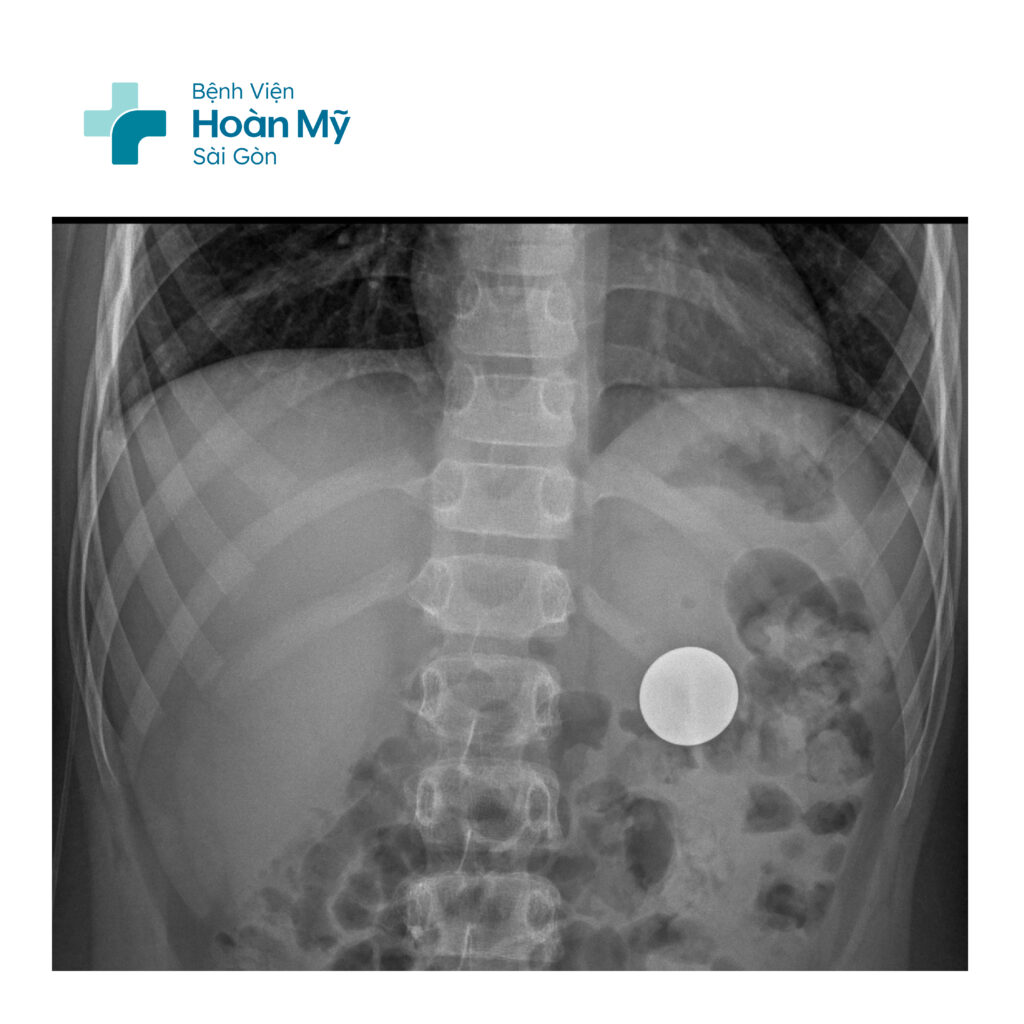

Tại bệnh viện, các bác sĩ ngay lập tức tiến hành thăm khám lâm sàng và nhận thấy bệnh nhi không có biểu hiện bất thường như đau bụng hay buồn nôn. Hình ảnh X-quang bụng cho thấy dị vật đã di chuyển vào dạ dày do phản xạ nuốt tự nhiên.

X-quang phát hiện dị vật, khả năng còn trong dạ dày

Tuy nhiên, do tình trạng dạ dày còn chứa nhiều thức ăn, khó phát hiện dị vật qua nội soi, đồng thời nhằm đảm bảo an toàn và tránh tai biến có thể xảy ra, đội ngũ y tế đã quyết định theo dõi, chờ thức ăn tiêu hóa một phần trước khi chỉ định nội soi dạ dày gây mê cho bệnh nhi với sự đồng thuận từ phía gia đình.